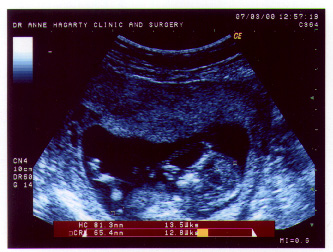

| And this one is a front view taken at 12 weeks. |